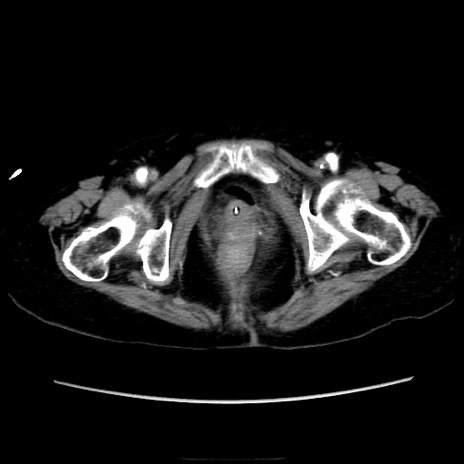

症例40(横断像)

【症例】90歳代女性

【主訴】腹痛・嘔吐

【現病歴】 食欲低下、嘔吐があり昨日他院受診。肺炎と診断され入院となる。入院後より腹部全体に圧痛あり。胃管留置され経過みていたが、症状持続するため、

当院転院となる。

【既往歴】胸椎圧迫骨折、胆石症

【身体所見】腹部:中央に激痛あり、圧痛あり、反跳痛不明

【データ】WBC 17100、CRP 18.82

横断像